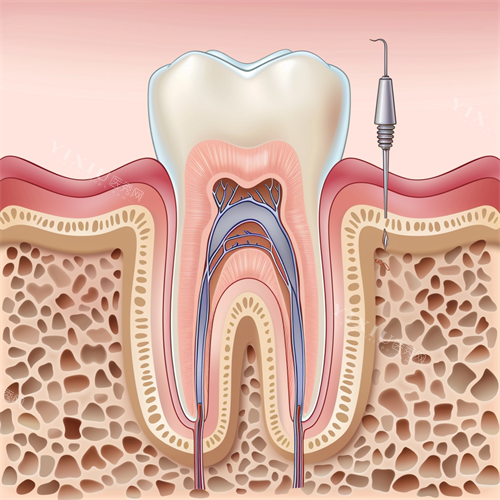

没过多久,我就见到了给我治疗的张医生。他仔细查看了我的牙片,又用工具检查了牙齿的情况,随后很耐心地跟我说:“你这牙髓已经发炎了,得做根管治疗。别担心,现在的技术很成熟,过程不会太难受的。” 接着,他拿出一个牙齿模型,边比划边给我解释根管治疗的步骤,就像和朋友聊天一样,把复杂的知识说得明明白白,让我心里有了底。

治疗过程中,比较让我惊讶的是他们用的设备。张医生操作着智能化根管治疗仪,旁边的屏幕上能清楚看到牙齿内部的情况。“你看,这就是发炎的牙髓,我们现在把它清理干净。” 看着屏幕上的画面,我心里不再像以前看牙时那样充满未知的恐惧,反而觉得有点新奇。整个治疗过程,张医生和护士配合得特别默契,每进行一个步骤,都会提前告诉我可能会有什么感觉,让我做好准备。